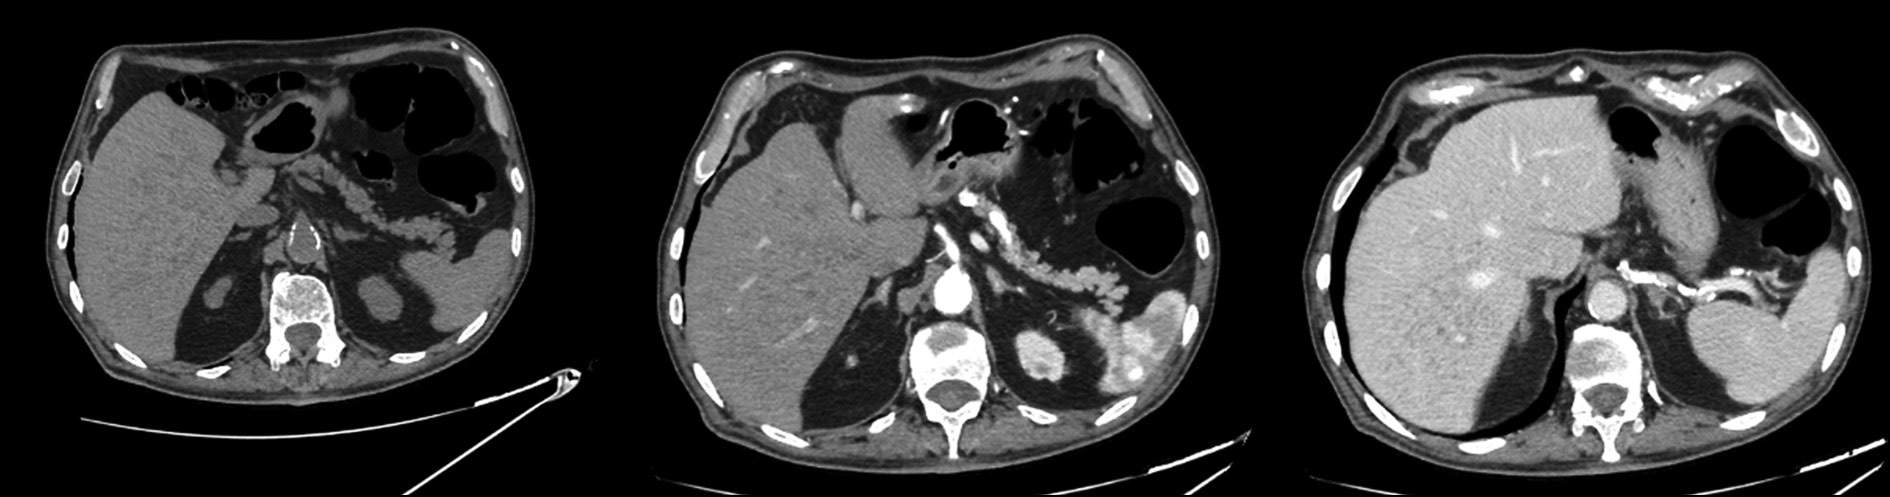

An unknown situs viscerum inversus totalis, accidentally discovered after computed tomography

Abstract

Benign situs inversus totalis of the viscerum is often diagnosed accidentally, rarely in adults, and more frequently in children and neonates, affecting both sexes. In this report, a young female patient accidentally discovered a situs inversus totalis after computed tomography for acute abdominal pain. In this uncommon anatomical abnormality, the major visceral organs are reversed in the opposite direction. This report highlights the importance of being aware of and considering situs inversus in clinical practice, particularly when interpreting imaging findings and planning medical procedures. This is critical for differential diagnosis and comorbidities that may affect those patients.

The cause of situs inversus totalis is still unknown; however, this condition is frequently asymptomatic, particularly in infants, and is sometimes associated with other syndromes. The patient arrived at the emergency department with left flank pain, nausea, and fever. In the first ultrasonography, a strange anatomy was suspected; thus, a contrasted computed tomography was performed. The patient had never had a computed tomography scan before. The identification of situs inversus totalis was unexpected and coincidental; the computed tomography images were carefully examined. In patients with chest or abdominal pain, clinicians may consider situs inversus totalis based on computed tomography, particularly if without clinical and imaging history. This knowledge can help in the differential diagnosis, avoiding unneeded interventions. Moreover, comorbidities that affect several systems, particularly cardiovascular and pulmonary systems, affect quite a few patients with situs inversus totalis, who require careful examination and lifelong monitoring.